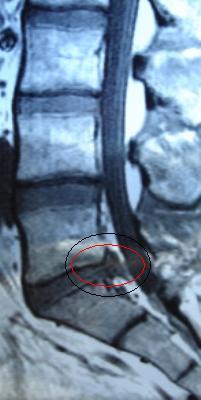

I also seem to have some proeminent vertebrae around, I think L4 or L5…and am now praying it isn’t spondylolisthesis.

P.S.:as soon as I get the X-ray done I’ll tell you if there’s any structural problem. btw, anyone else have proeminent vertebrae troughout the spine?